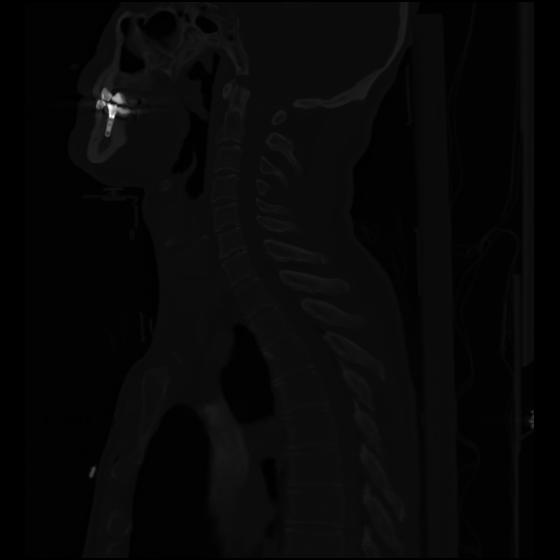

24 ANGIO,CE,Sag-MIP,5.000,ANGIO,Sag-MIP,